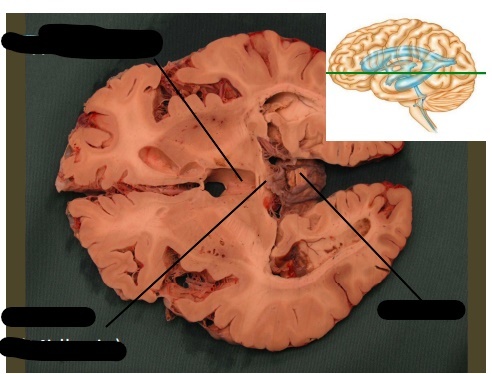

label, note important features

only portion of corona radiata seen right now are association fibers (which interconnect ipsilateral gyri) there are no internal capsule or lateral ventricles seen, indicating this cut is very rostral (pre-frontal cortex)